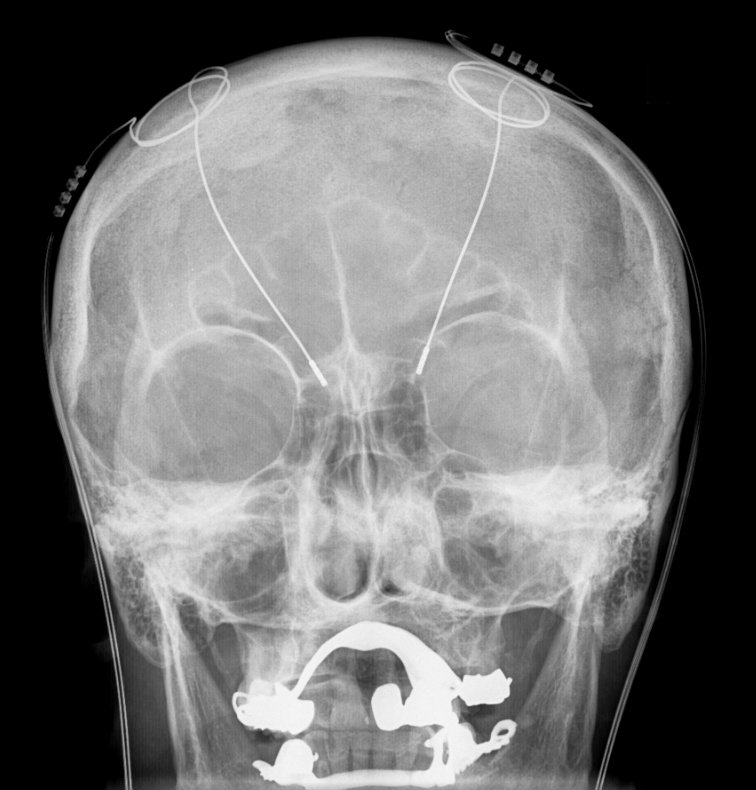

如我们之前讨论的一样,下面是介绍6009-Catena映射的示意图。我要把这幅图给山高主管看,来让他给我们项目分配点资金……SCP基金会是如此庞大又强力的机构,想从它们手里榨出一点钱来总是那么痛苦。我肯定不会羡慕基金会会计员的生活。

图是我自己画的。很遗憾,它有点粗糙,但我觉得能说明问题。我把它发给了我们的绘图团队,但我不期待他们能及时回复我。